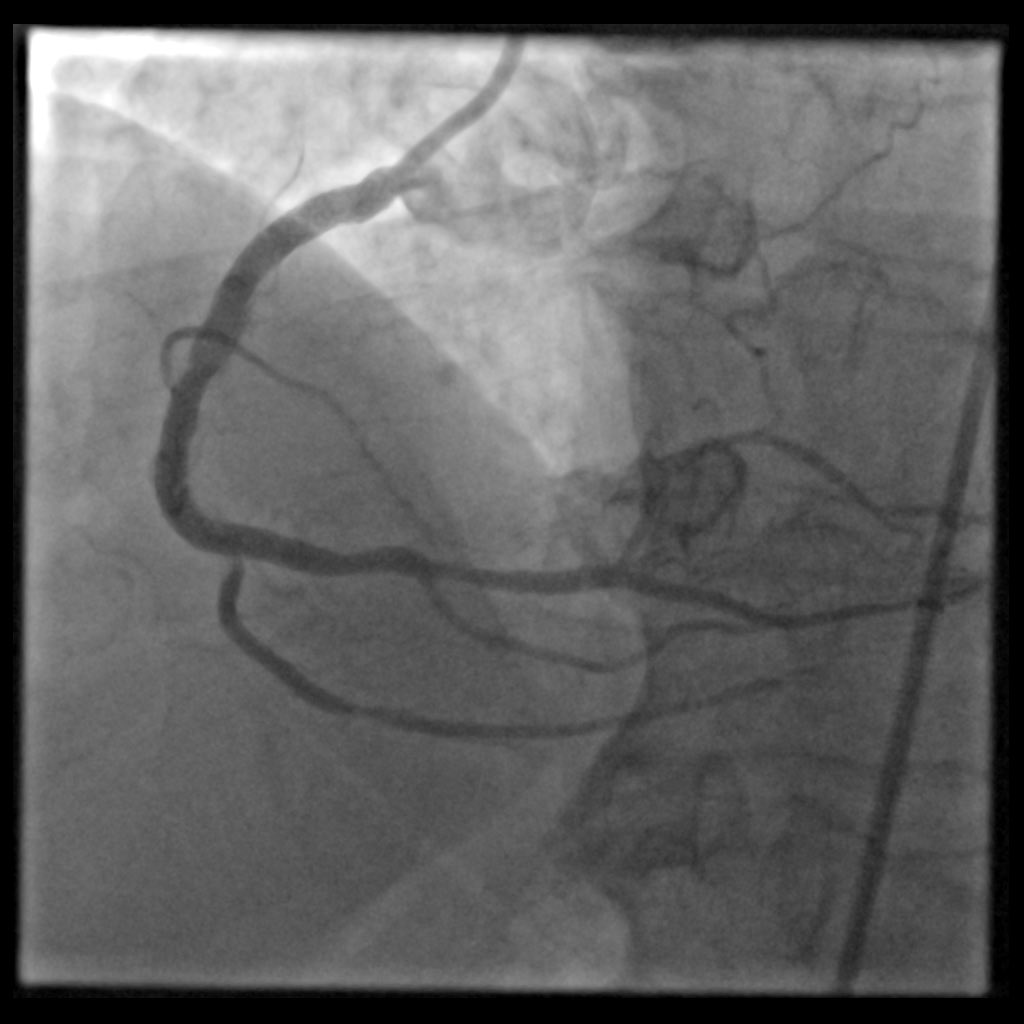

A 63 y.o female presented with NSTEMI. One year before CTA with normal LAD/RCA and mild lesion in OM1. Here is the angio and OCT images. What would you do?